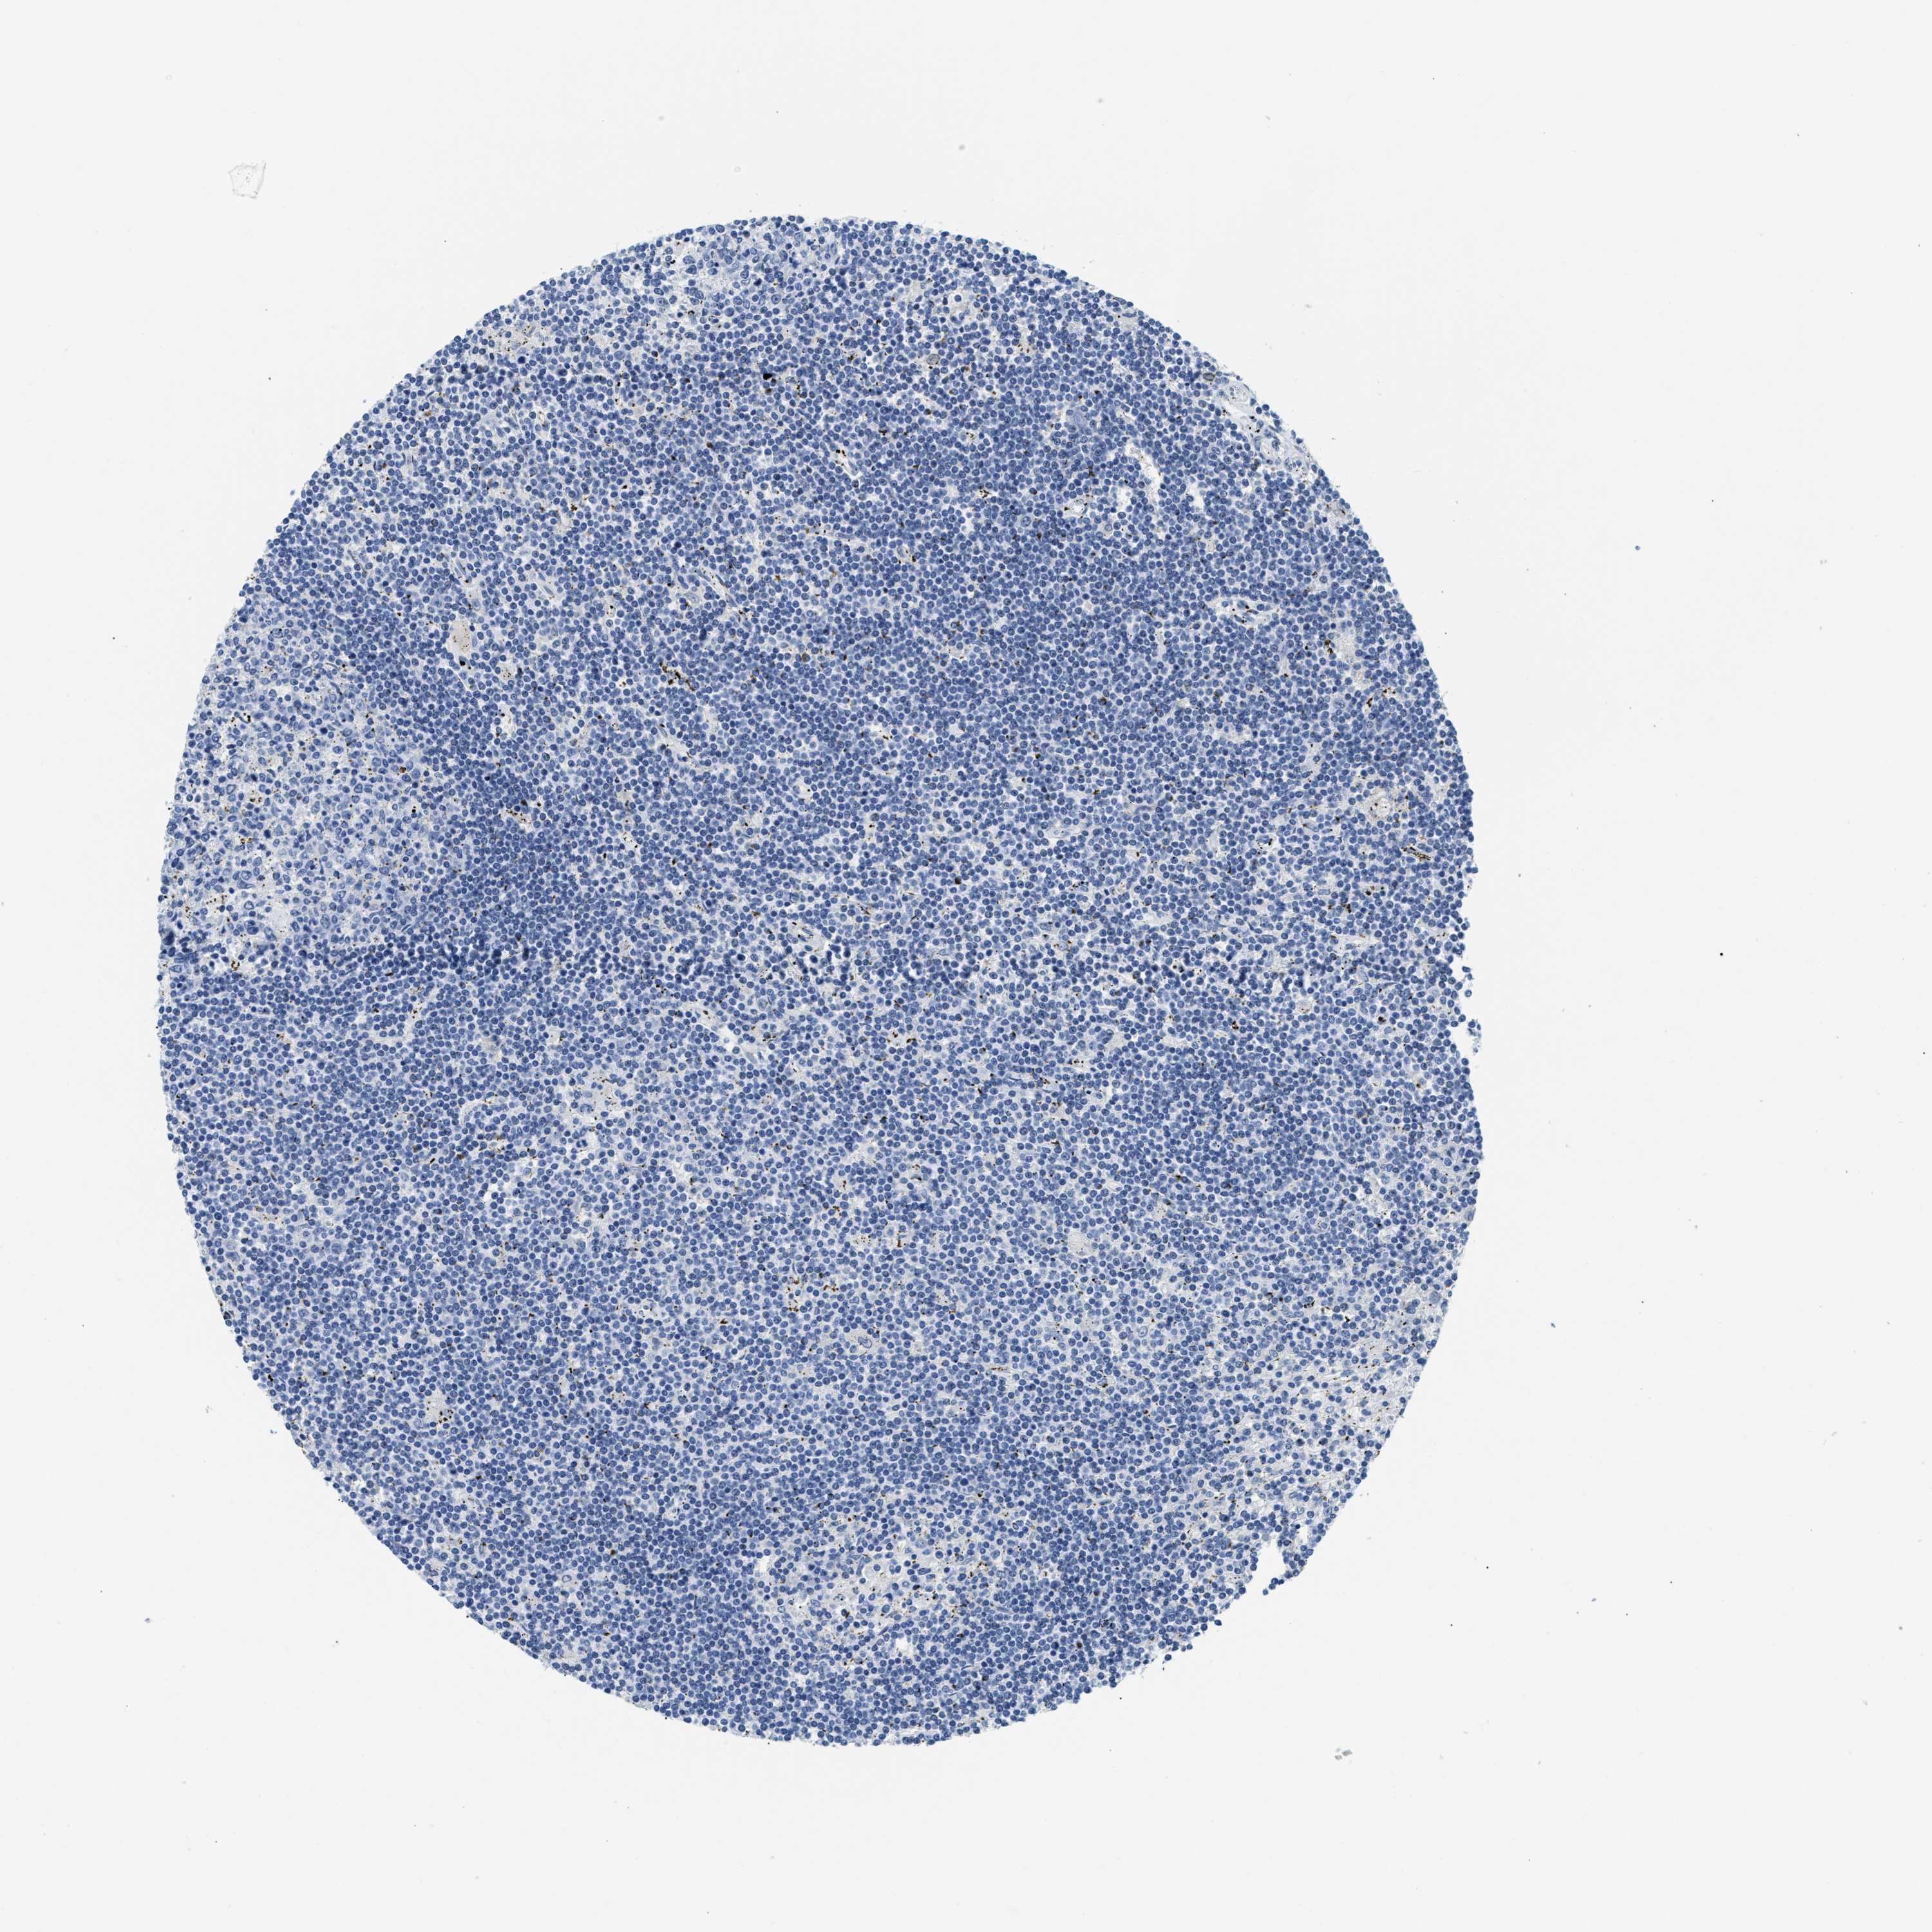

LYMPHOMA - Protein expressioni

A mouse-over function shows sample information and annotation data. Click on an image to view it in a full screen mode. Samples can be filtered based on level of antibody staining by selecting one or several of the following categories: high, medium, low and not detected. The assay and annotation is described here.

Antibody stainingi

Antibody staining in the annotated cell types in the current human tissue is reported as not detected, low, medium, or high, based on conventional immunohistochemistry profiling in selected tissues. This score is based on the combination of the staining intensity and fraction of stained cells.

Each image is clickable and will lead to virtual microscopy that enables deeper exploration of all samples and also displays staining intensity scores, fraction scores and subcellular localization as well as patient and tissue information for each sample.

Antibody HPA048761

Antibody HPA058627

Antibody CAB020709

Malignant lymphoma, non-Hodgkin's type, Low grade

Malignant lymphoma, non-Hodgkin's type, High grade

Hodgkin's disease, NOS